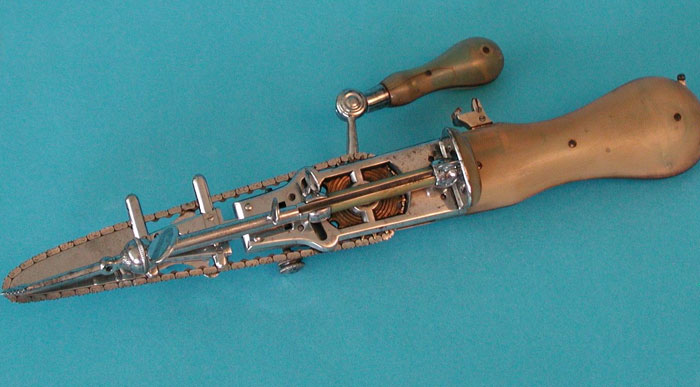

#8

The chainsaw was invented as a tool to aid in childbirth. Rotating blades to get through the pelvic bone…..

Image credits: WeThePeeps2020